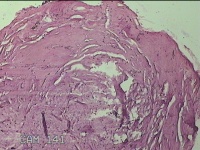

右下腹部切口结节

性别

女

年龄

27岁

临床诊断

皮下结节

一般病史

发现右下腹部切口结节10余年。

标本名称

大体所见

灰白暗红色带皮肤样结节2.3x1.3x0.8cm一个。表面糜烂,切面灰白色,质硬。

需要侵袭性纤维瘤病和纤维瘢痕鉴别一下